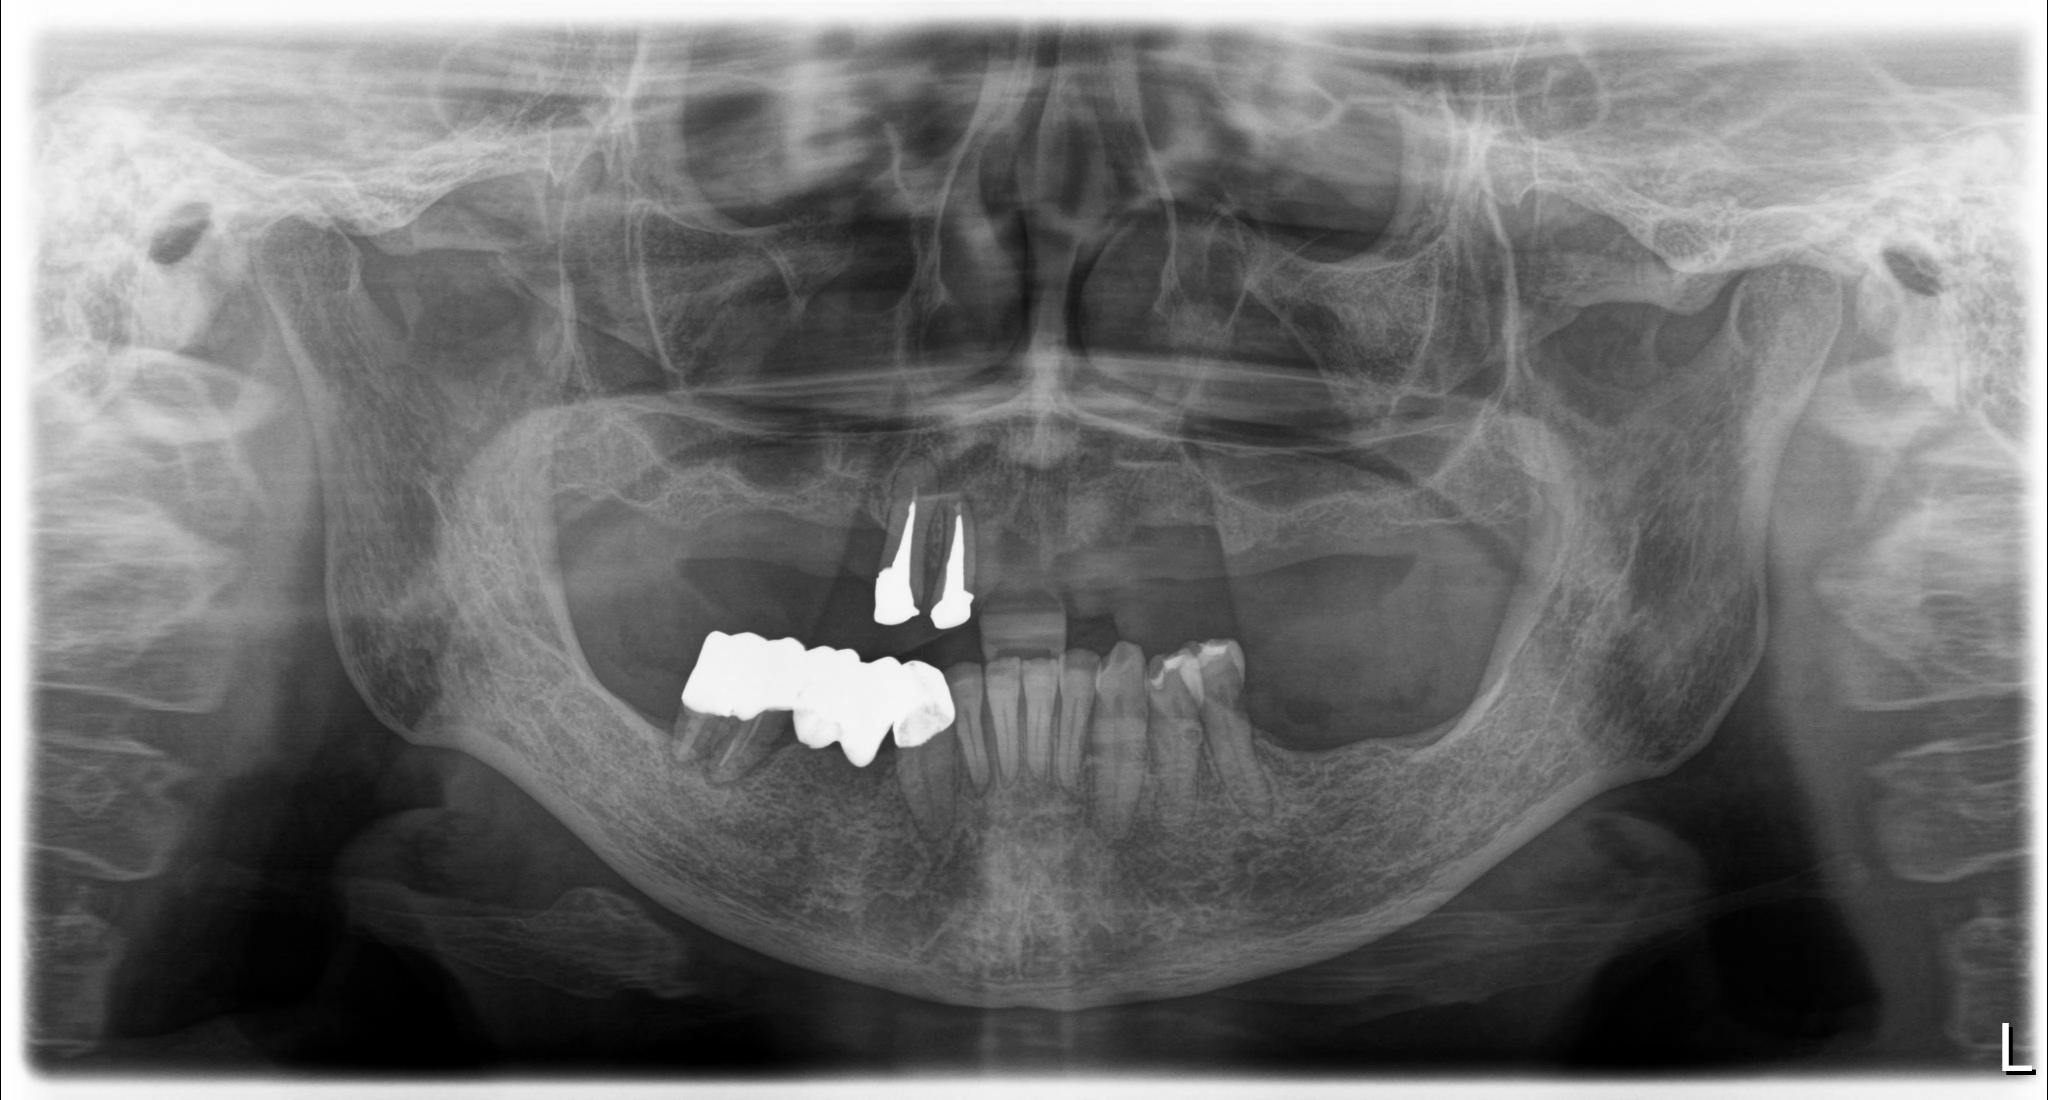

術前

内容 :上下顎オールオン4ザイゴマ2

費用 :4,963,200円

※モニター価格

期間 :半年

リスク:出血・腫れ・痺れ・痛み